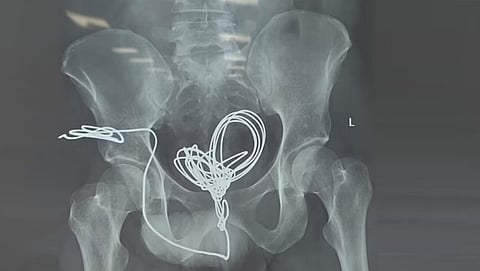

തിരുവനന്തപുരം: ഇരുപത്തഞ്ചുകാരന്റെ മൂത്രനാളിയില് മൂന്നുമീറ്ററോളം നീളമുള്ള ഇലക്ട്രിക് ഇന്സുലേഷന് വയര് അപൂര്വ ശസ്ത്രക്രിയയിലൂടെ പുറത്തെടുത്തു. തിരുവനന്തപുരം മെഡിക്കല് കോളജ് ആശുപത്രിയില് രണ്ടര മണിക്കൂറോളം നീണ്ട ശസ്ത്രക്രിയയിലൂടെയാണ് യുവാവിന്റെ ജീവന് രക്ഷിച്ചത്. ഇലക്ട്രിക് വയര് പല കഷണങ്ങളായി മുറിച്ചാണ് യൂറോളജി വിഭാഗത്തിലെ ഡോക്ടര്മാര് പുറത്തെടുത്തത്.

ഇലക്ട്രിക് ഇന്സുലേഷന് വയര് യുവാവ് സ്വയം കുത്തിക്കയറ്റുകയായിരുന്നു. ആശുപത്രിയിലെത്തുമ്പോള് ഇലക്ട്രിക് വയര് മൂത്രസഞ്ചിയില് കുരുങ്ങിക്കിടക്കുന്ന നിലയിലായിരുന്നു. എന്തിനാണ് യുവാവ് ഇങ്ങനെ ചെയ്തതെന്ന കാരണം വ്യക്തമല്ല. ശസ്ത്രക്രിയയ്ക്കു ശേഷം തീവ്രപരിചരണ വിഭാഗത്തില് ചികിത്സയില് കഴിയുന്ന യുവാവ് സുഖം പ്രാപിച്ചു വരുന്നു.